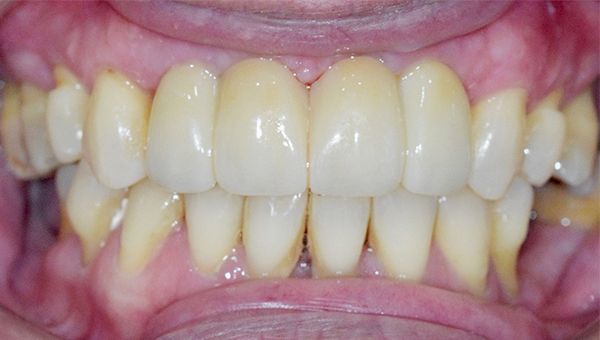

강*란 임플란트 시술 사례

전체 임플란트

2025.02.07

치료 전

2025.08.19

치료 후